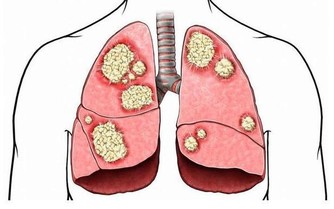

隨著我國現代化的發展趨勢越來越快,工業污染愈加嚴重,肺癌的發病率越來越高,並有年輕化趨勢。大量資料表明,長期生活在大氣污染的環境及大量吸煙均與肺癌的發病率有著非常密切的關係,因此應該大力提倡不吸煙,並加強環境治理。

一是咳嗽,最為常見的是原因不明的干咳、嗆咳等,以咳嗽為始發症狀的患者約為二分之一至三分之二。

二是胸痛,表現為不規則的鈍痛、悶痛、隱痛,部位不一定,與呼吸的關係也不確定。

三是發熱,表現為癌性發熱,是肺癌腫瘤壞死所產生的毒素引起的癌性發熱,程度不一,輕者僅有低熱,重者則有高熱,用藥後可暫時好轉,但很快又會復發。

四是反复“肺炎”,由於腫物在支氣管管腔內的佔位而引起的肺部炎症,像是重感冒的症狀,反復出現類似肺炎的症狀。

五是聲音嘶啞,患者表現為聲音嘶啞症狀,其實是肺部出現了腫瘤,縱隔淋巴結轉移,腫大的淋巴結壓迫了喉返神經引起聲帶麻痺,導致聲音嘶啞。

六是吞嚥困難,患者表現為吃東西吞嚥困難。食管和肺距離很近,所以肺部的腫瘤進展就出現了縱隔淋巴結轉移。轉移的淋巴結進一步腫大就會壓迫到食管,導致吞嚥不舒服以及吞嚥困難。

以上為肺癌最為明顯的早期症狀,對患者來說,如果能夠及早發現,及早預防,及早治療,是可以有效抵制癌細胞進一步擴散,以達到治療效果。